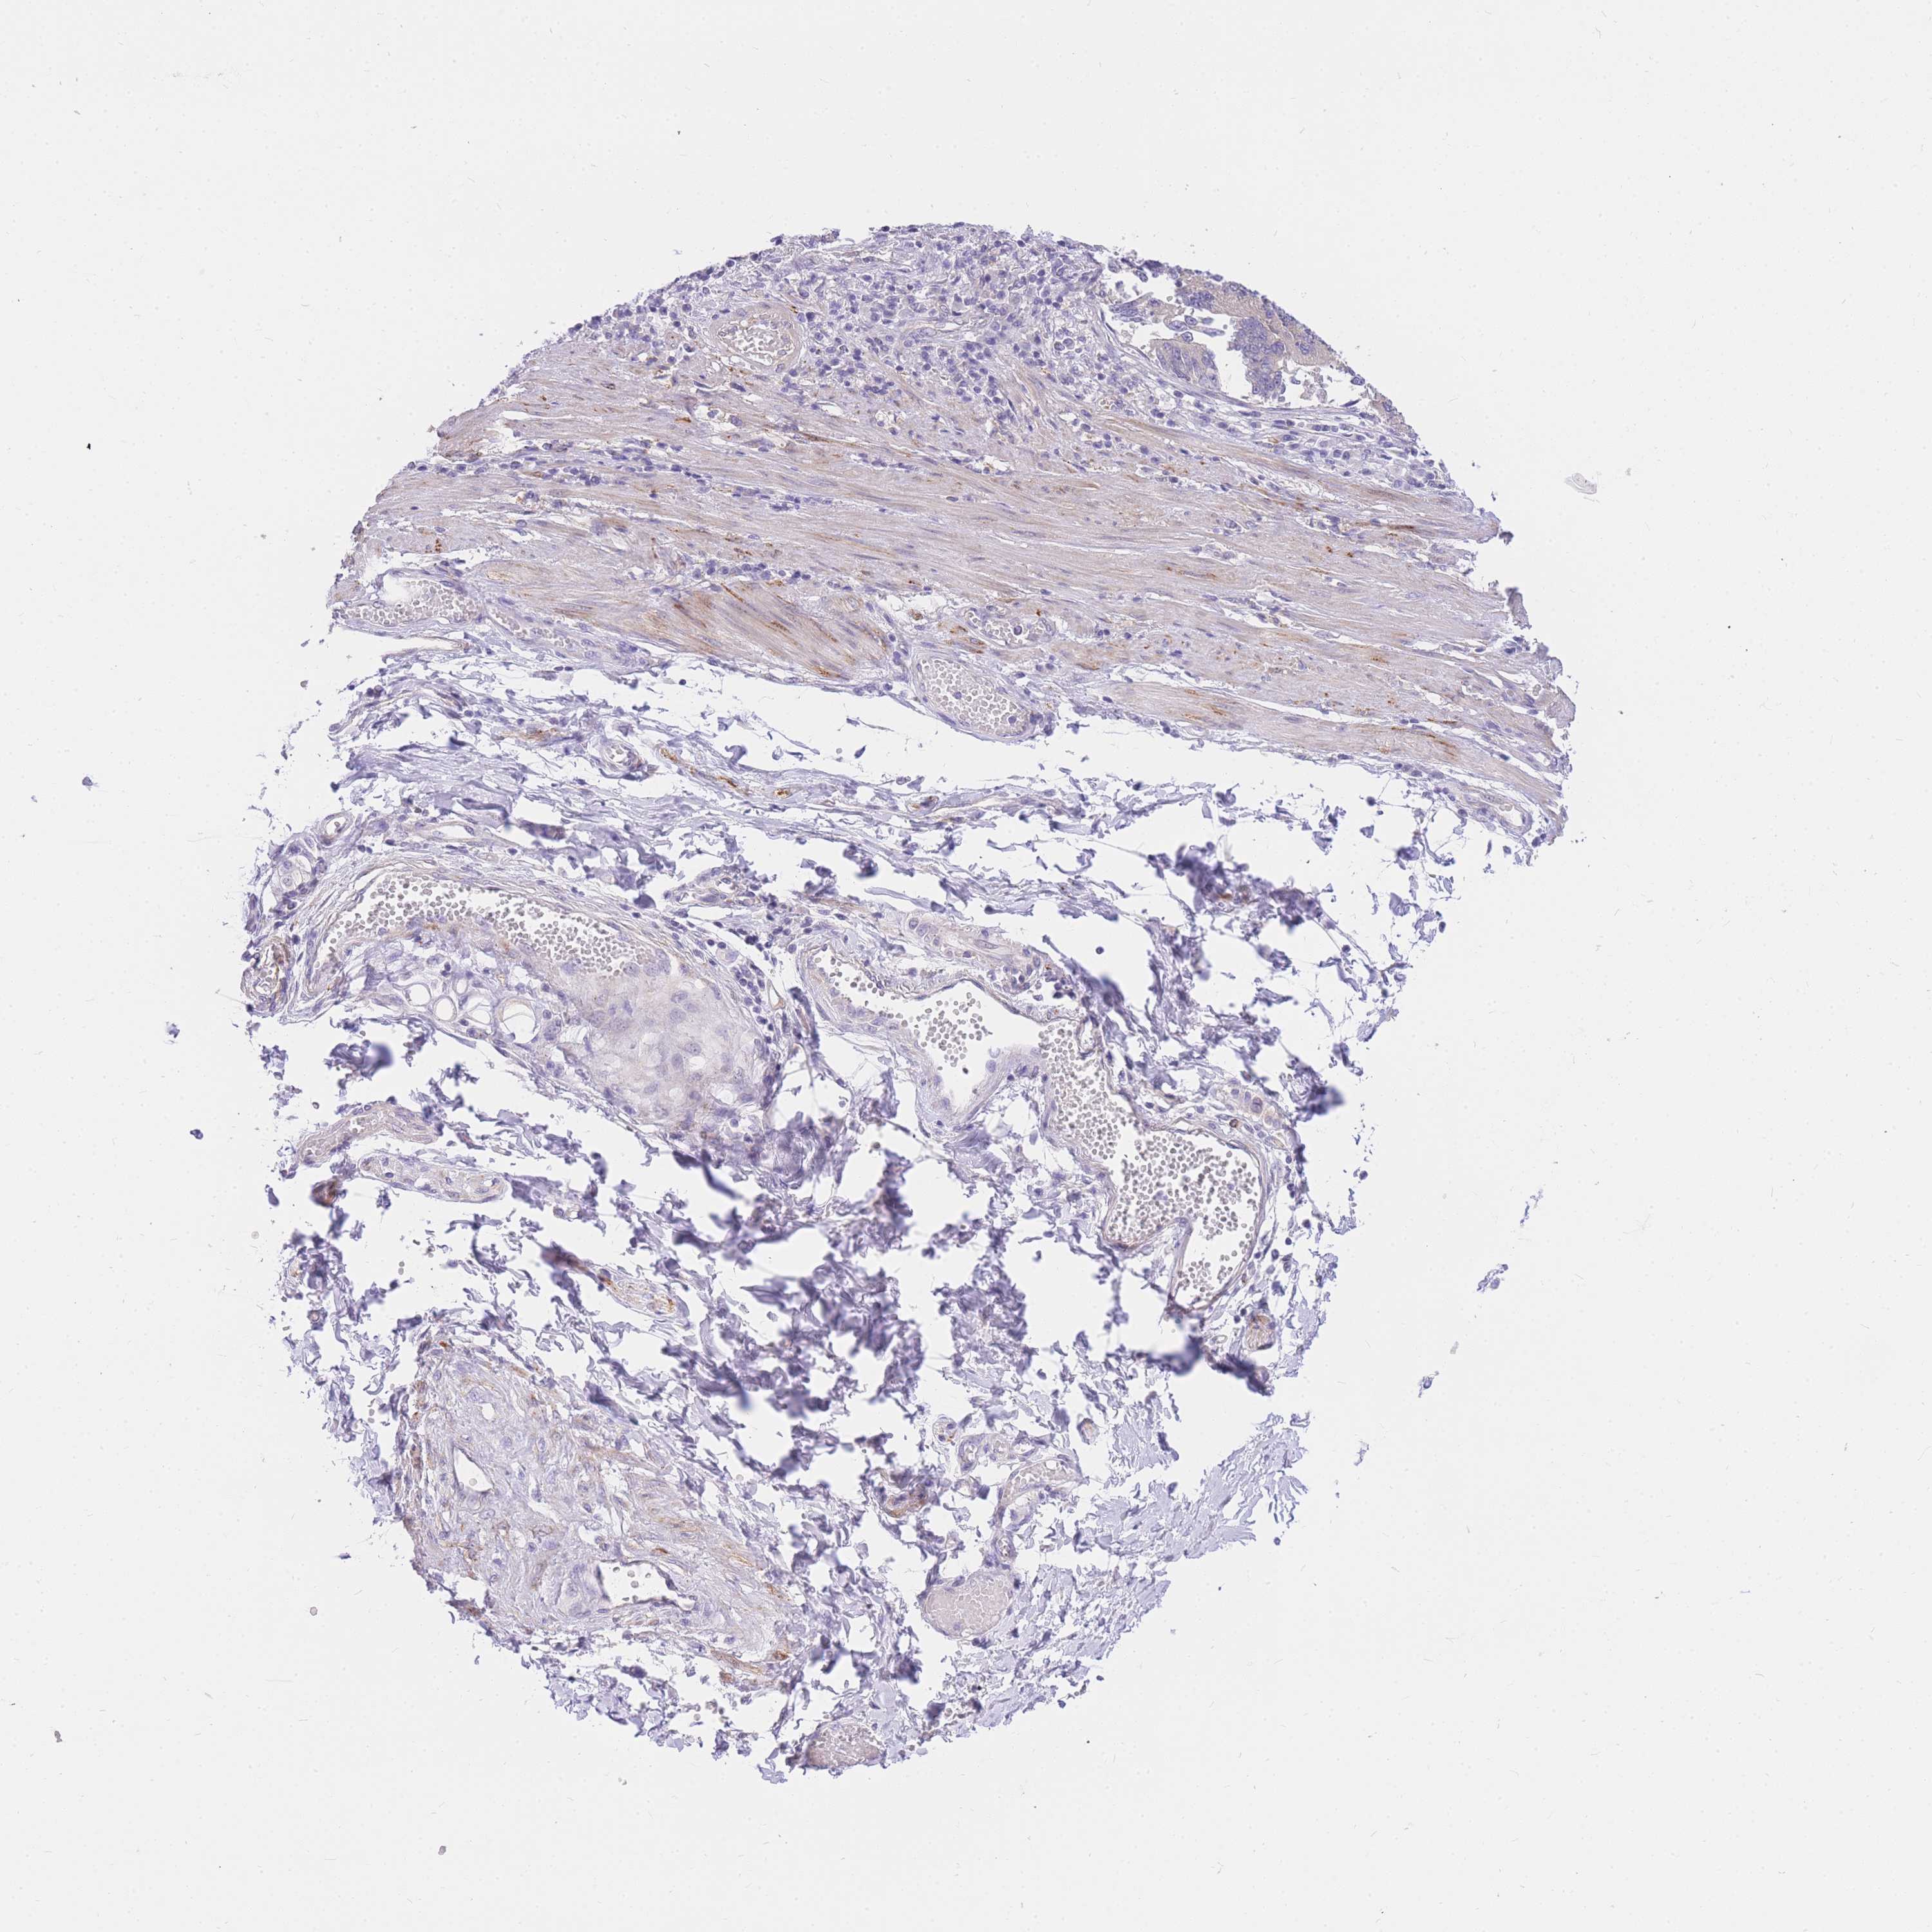

STOMACH CANCER - Protein expressioni

A mouse-over function shows sample information and annotation data. Click on an image to view it in a full screen mode. Samples can be filtered based on level of antibody staining by selecting one or several of the following categories: high, medium, low and not detected. The assay and annotation is described here.

Antibody stainingi

Antibody staining in the annotated cell types in the current human tissue is reported as not detected, low, medium, or high, based on conventional immunohistochemistry profiling in selected tissues. This score is based on the combination of the staining intensity and fraction of stained cells.

Each image is clickable and will lead to virtual microscopy that enables deeper exploration of all samples and also displays staining intensity scores, fraction scores and subcellular localization as well as patient and tissue information for each sample.

Antibody HPA027242

Antibody HPA027328

Staining

High

Medium

Low

Not detected

Intensity

Strong

Moderate

Weak

Negative

Quantity

>75%

75%-25%

<25%

None

Location

Nuclear

Cytoplasmic/membranous

Cytoplasmic/membranous,nuclear

Adenocarcinoma, NOS